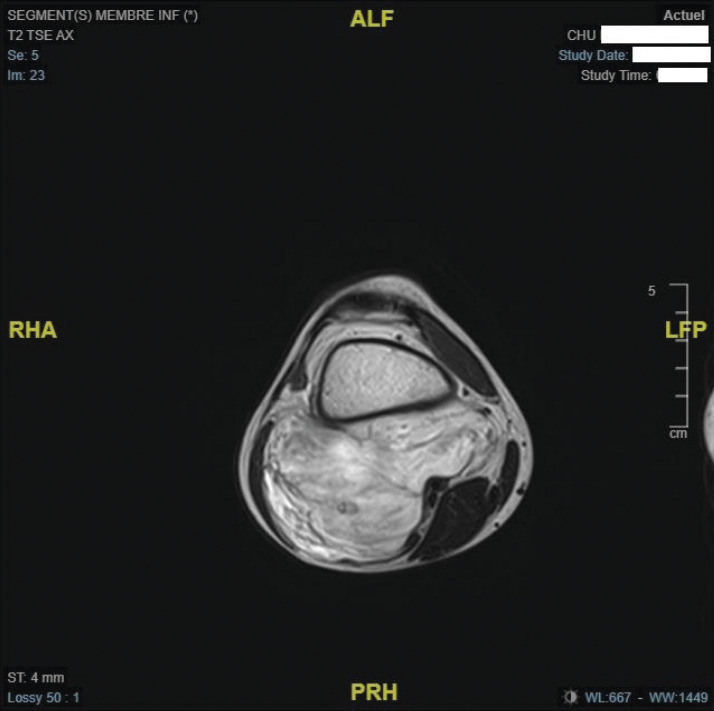

L’IRM confirme l’existence d’une masse tissulaire avec contingent graisseux refoulant les structures de voisinage (figures ).

L’IRM confirme l’existence d’une masse tissulaire avec contingent graisseux refoulant les structures de voisinage (

L’IRM est l’examen d’imagerie de choix pour préciser la localisation et les rapports de la lésion. Si elles sont réalisées, la radiographie ne montre pas de lyse osseuse et l’échographie met en évidence une masse hétérogène à contenu graisseux.